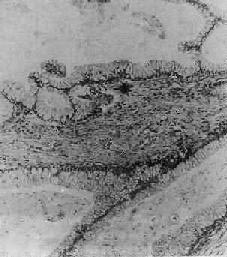

系統性紅斑狼瘡所致精神病病變圖1、關節檢查以發現關節炎或肌腱炎的表現。